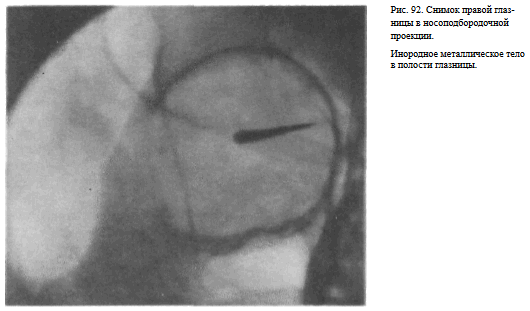

На прицельном снимке каждой из глазниц в этой же проекции, как правило, небольшие изменения структуры стенок, а также мелкие инородные тела глаза видны лучше. Такие снимки широко используют в офтальмологической практике (рис. 92).

СНИМОК ГЛАЗНИЦЫ В НОСОЛОБНОЙ ПРОЕКЦИИ

Назначение снимка — изучение контуров костей, образующих вход в глазницу, структуры верхней и наружной ее стенок, ширины и контуров верхних глазничных щелей, а также выявление инородных тел в полости глазницы.

Укладка больного для выполнения снимка, информативность снимка, критерии правильности технических условий съемки и правильности укладки те же, что для снимка крыльев клиновидной кости и верхних глазничных щелей.

В качестве примера информативности снимка глазниц в носолобной проекции для выявления инородных тел глаза и деструктивных изменений стенок приводим два наблюдения.

Одно из них — случай ранения глаза металлической стружкой (рис. 93), другое — случай деструкции верхненаружного края глазницы при доброкачественной опухоли слезной железы (рис. 94).